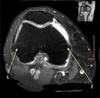

1

Not at all

2

3

4

5

Perfectly

Q

What is letter B?

A

DELTOID MUSCLE